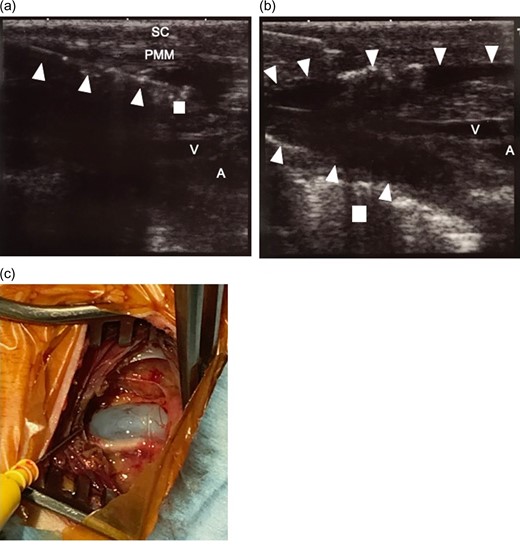

Intra-operative ultrasound examination for confirming the position of organs before infusion of tumescent local analgesia solution. The thickness of the subcutaneous tissue, 2.6 mm; and pectoralis major muscle, 5.6 mm. (a) The right side of the picture is the superior (head) side of the patient. (b) The right side of the picture is the right side of the patient. SC, subcutaneous tissue; PMM, pectoralis major muscle; V, axillary vein; A, axillary artery.